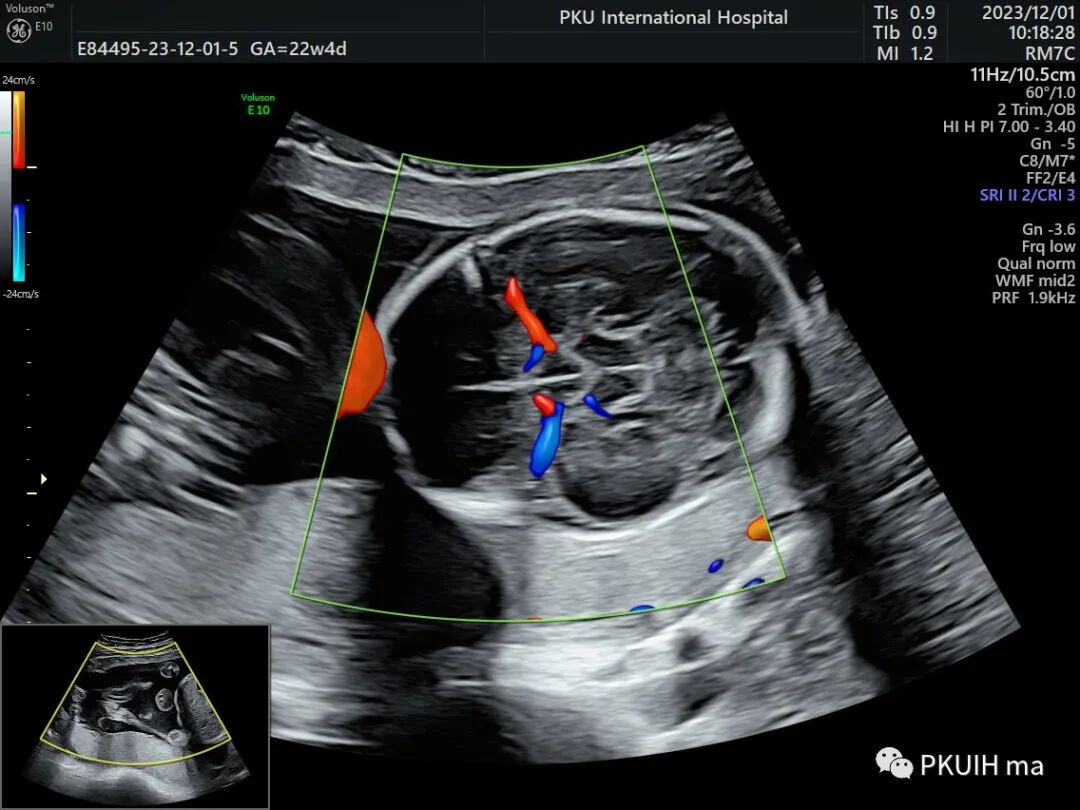

GE的SlowFlow功能还是有作用的。看看下面这几张,第一第二张图用CD和HD都不能完美的显示胎儿大脑Willis环,采用SlowFlow功能能够显示完整的颅底动脉环

通过这个血流成像前交通后交通都能完美显示